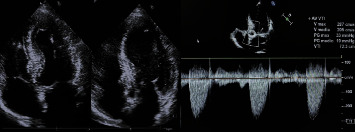

Abstract Image